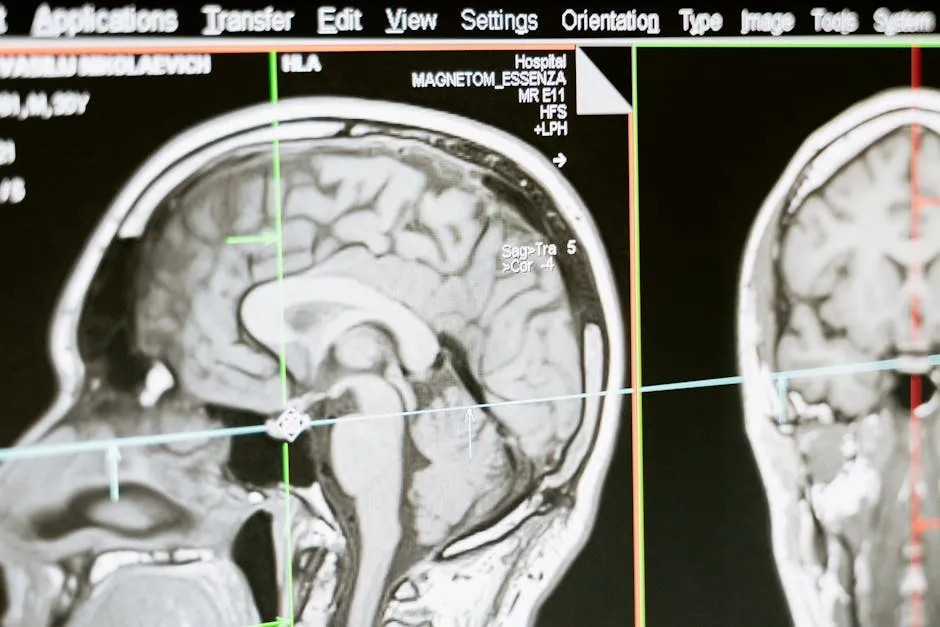

高尿酸也可能引發心腦血管疾病

除了痛風,高尿酸還可能引發高血壓、冠狀動脈心臟病、腦中風中等心腦血管疾病。高尿酸會加劇血管內皮的損傷,促使動脈粥狀硬化加重,增加心臟和腦血管疾病的風險。如果你是個高尿酸患者,你得注意了,心臟和腦袋可都在承受它的威脅。